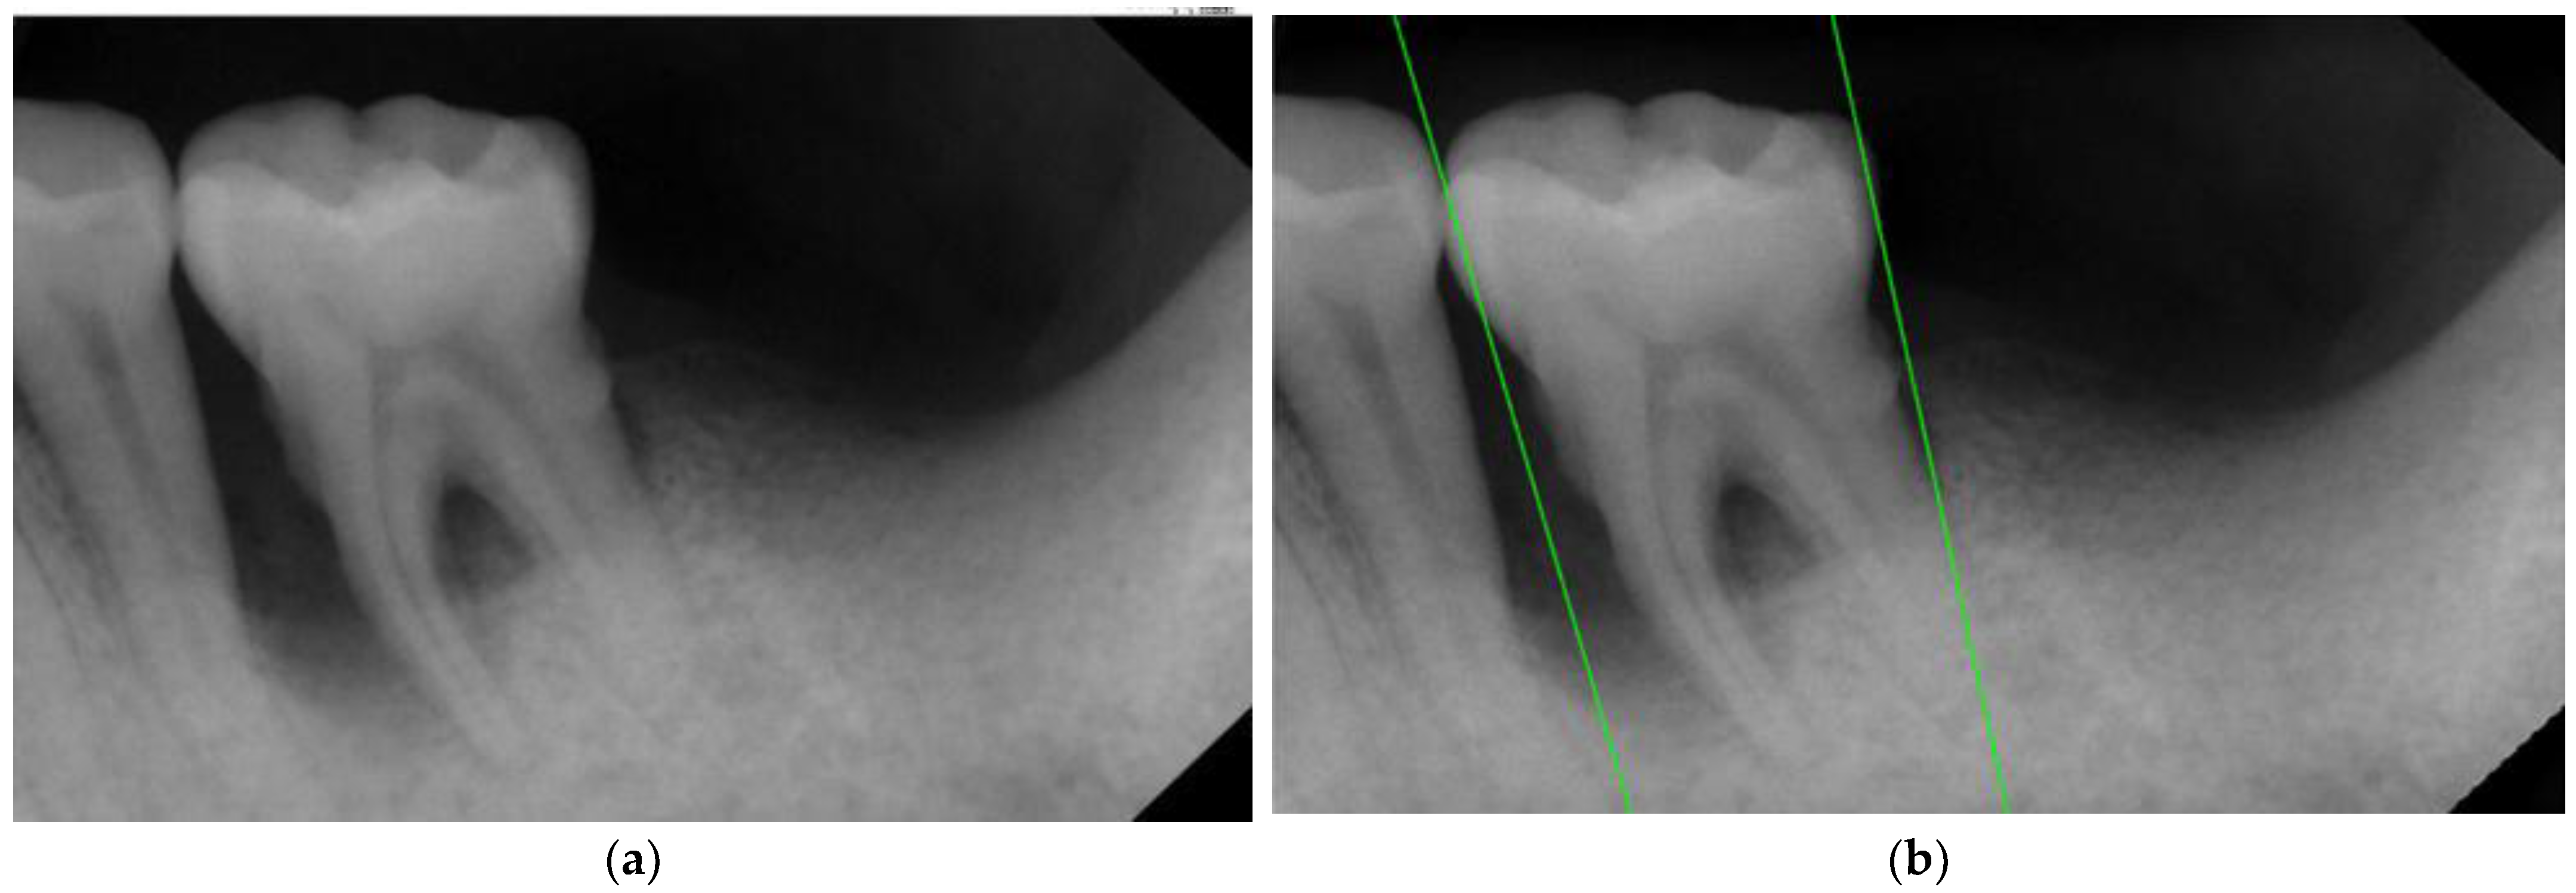

| Original Images | Gaussian High-Pass Filter | Gaussian High-Pass Filter + Mask | |

|---|---|---|---|

| Validation Accuracy | 84.16% | 87.21% | 94.97% |

| Validation Loss | 0.7634 | 0.4578 | 0.1822 |

| Model | GoogLeNet | GoogLeNet | GoogLeNet |

| Image | ![]() | ![]() | ![]() |